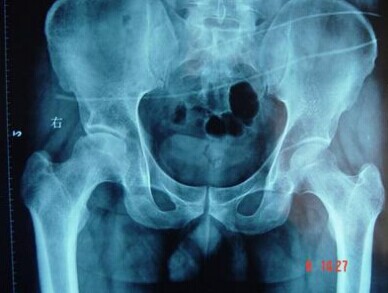

(1)创伤性髋关节脱位:有可能造成圆韧带血管和支持带血管的损伤。已有报道称髋关节脱位后股骨头坏死的发生率是25%,Hastrings等报道一组125例病人中,发生在股骨颈骨折之后者78%,在髋关节脱位之后者为6%,有2%的病例为既无骨折也无脱位后的髋部创伤。>>>>患上股骨头坏死怎么办?怎么治疗好?

儿童的创伤性髋关节脱位后股骨头缺血性坏死的发生率为4%—10%,儿童较成年人的股骨头缺血性坏死发病率低。创伤性髋关节脱位造成缺血坏死与受伤时的年龄、有效复位的时间(不超过24h)、髋关节损伤的严重程度、合并有髋臼骨折、延误了诊断、或过早负重等因素有关。

(3)股骨头的无菌性坏死在先天性髋关节脱位中发生率可高达68%。这种并发症可受治疗方法和治疗中所固定位置的影响。极度外展位固 定可导致血管结构的梗死和对股骨头的过度压力。在治疗一侧髋关节脱位时,将两侧髋关节同时做固定之后,在正常侧也可发现有股骨头缺血性坏死,而在正常侧未行固定者则很少发生股骨头的缺血性坏死。